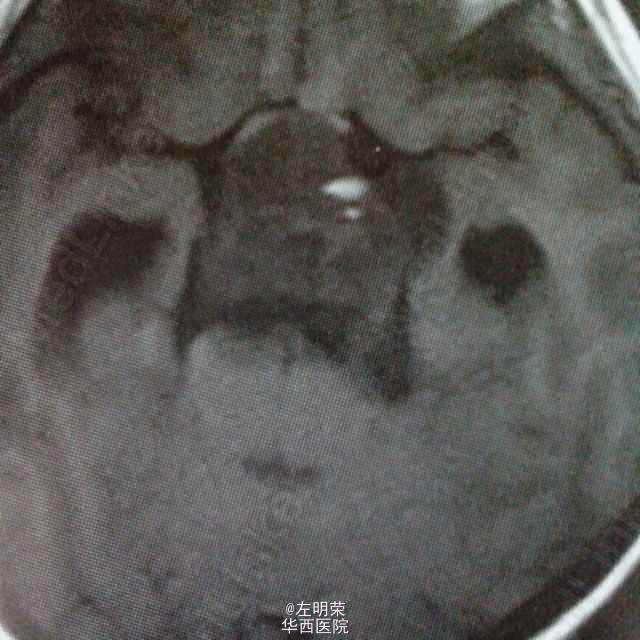

女,6岁,以间断头痛3个月余,加重2个月之主诉入院。MRI示:桥前池-鞍上池-三脑室内巨大不规则均匀强化影,鞍背骨质可见破坏,病灶内可见囊变坏死区。可见脑干及病灶周围实质明显受压移位,病灶与脑实质分界清楚;考虑诊断脊索瘤,颅咽管瘤,神经鞘瘤。术中见肿瘤囊实性,血供丰富,边界尚清,位于鞍背上方,脑干前方,与基底动脉,大脑后动脉粘连紧密,给予全部切除;病理示:神经鞘瘤。